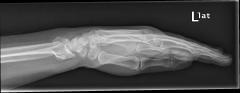

Περίπτωση 1ου ασθενούς